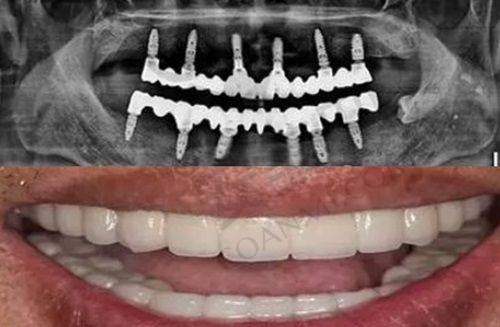

种植牙是目前修复缺失牙比较理想的方式,玉溪舒尔口腔门诊部在种植牙技术方面表现出色。前面已经提到,其拥有专精的种植医师团队,能够根据患者的口腔情况和身体状况,制定个性化的种植方案。在手术过程中,医生操作熟练,能够精细地将种植体植入到合适的位置,确保种植体与牙槽骨的良好结合。

而且,有患者反馈,玉溪舒尔口腔种植牙挺好的,医生技术娴熟收费不高,术后假牙稳定耐用。这说明门诊部在种植牙技术上不仅确保了质量,还在价格方面具有一定的优势,让更多患者能够享受到优质的种植牙服务。

牙齿修复也是口腔诊疗中的重要项目,对于那些牙齿缺损、缺失的患者来说至关重要。有患者表示,玉溪舒尔口腔牙齿修复技术太强大,为其解决了困扰已久的牙齿问题。多年来苦于牙齿缺损和修复问题的患者,在玉溪舒尔口腔得到了有效的治疗。这表明门诊部的医生在牙齿修复方面具有丰富的经验和高超的技术,能够根据不同患者的牙齿情况,选择合适的修复方法,如烤瓷牙、全瓷牙等,修复牙齿的外观和功能。